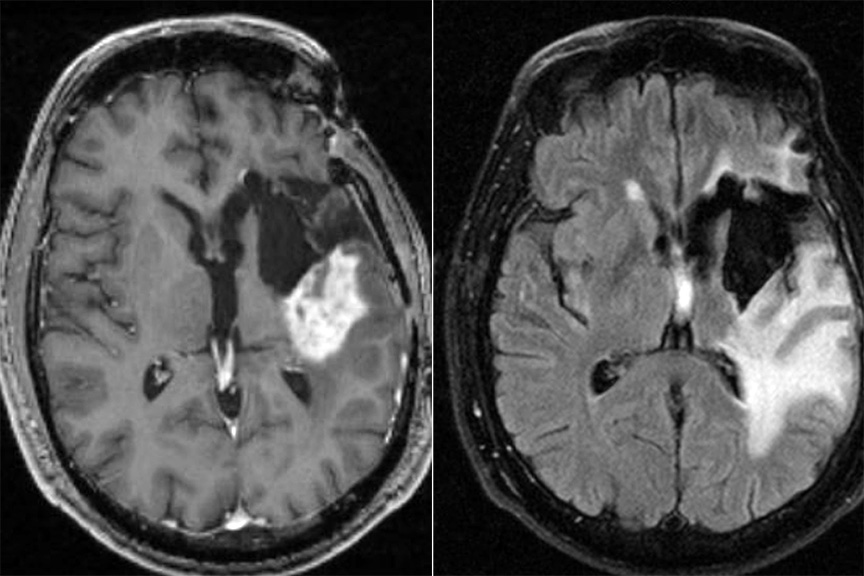

胶质母细胞瘤是最严重的脑癌类型之一,并且正在对患有该疾病的小鼠进行新的疗法。

新型摄影疗法的试验还表明,该治疗触发了一种免疫反应,可以在将来靶向癌细胞的免疫系统,这表明它可以防止胶质母细胞瘤在手术后返回。研究人员现在还正在研究儿童癌症神经母细胞瘤的新治疗方法。

“我们的研究表明,使用荧光标记物,杂物蛋白和近红外光的新型摄影疗法治疗可以鉴定和治疗小鼠中剩余的胶质母细胞瘤细胞。将来,我们希望这种方法也可以用来治疗人类胶质母细胞瘤和可能的其他癌症。”他补充说。